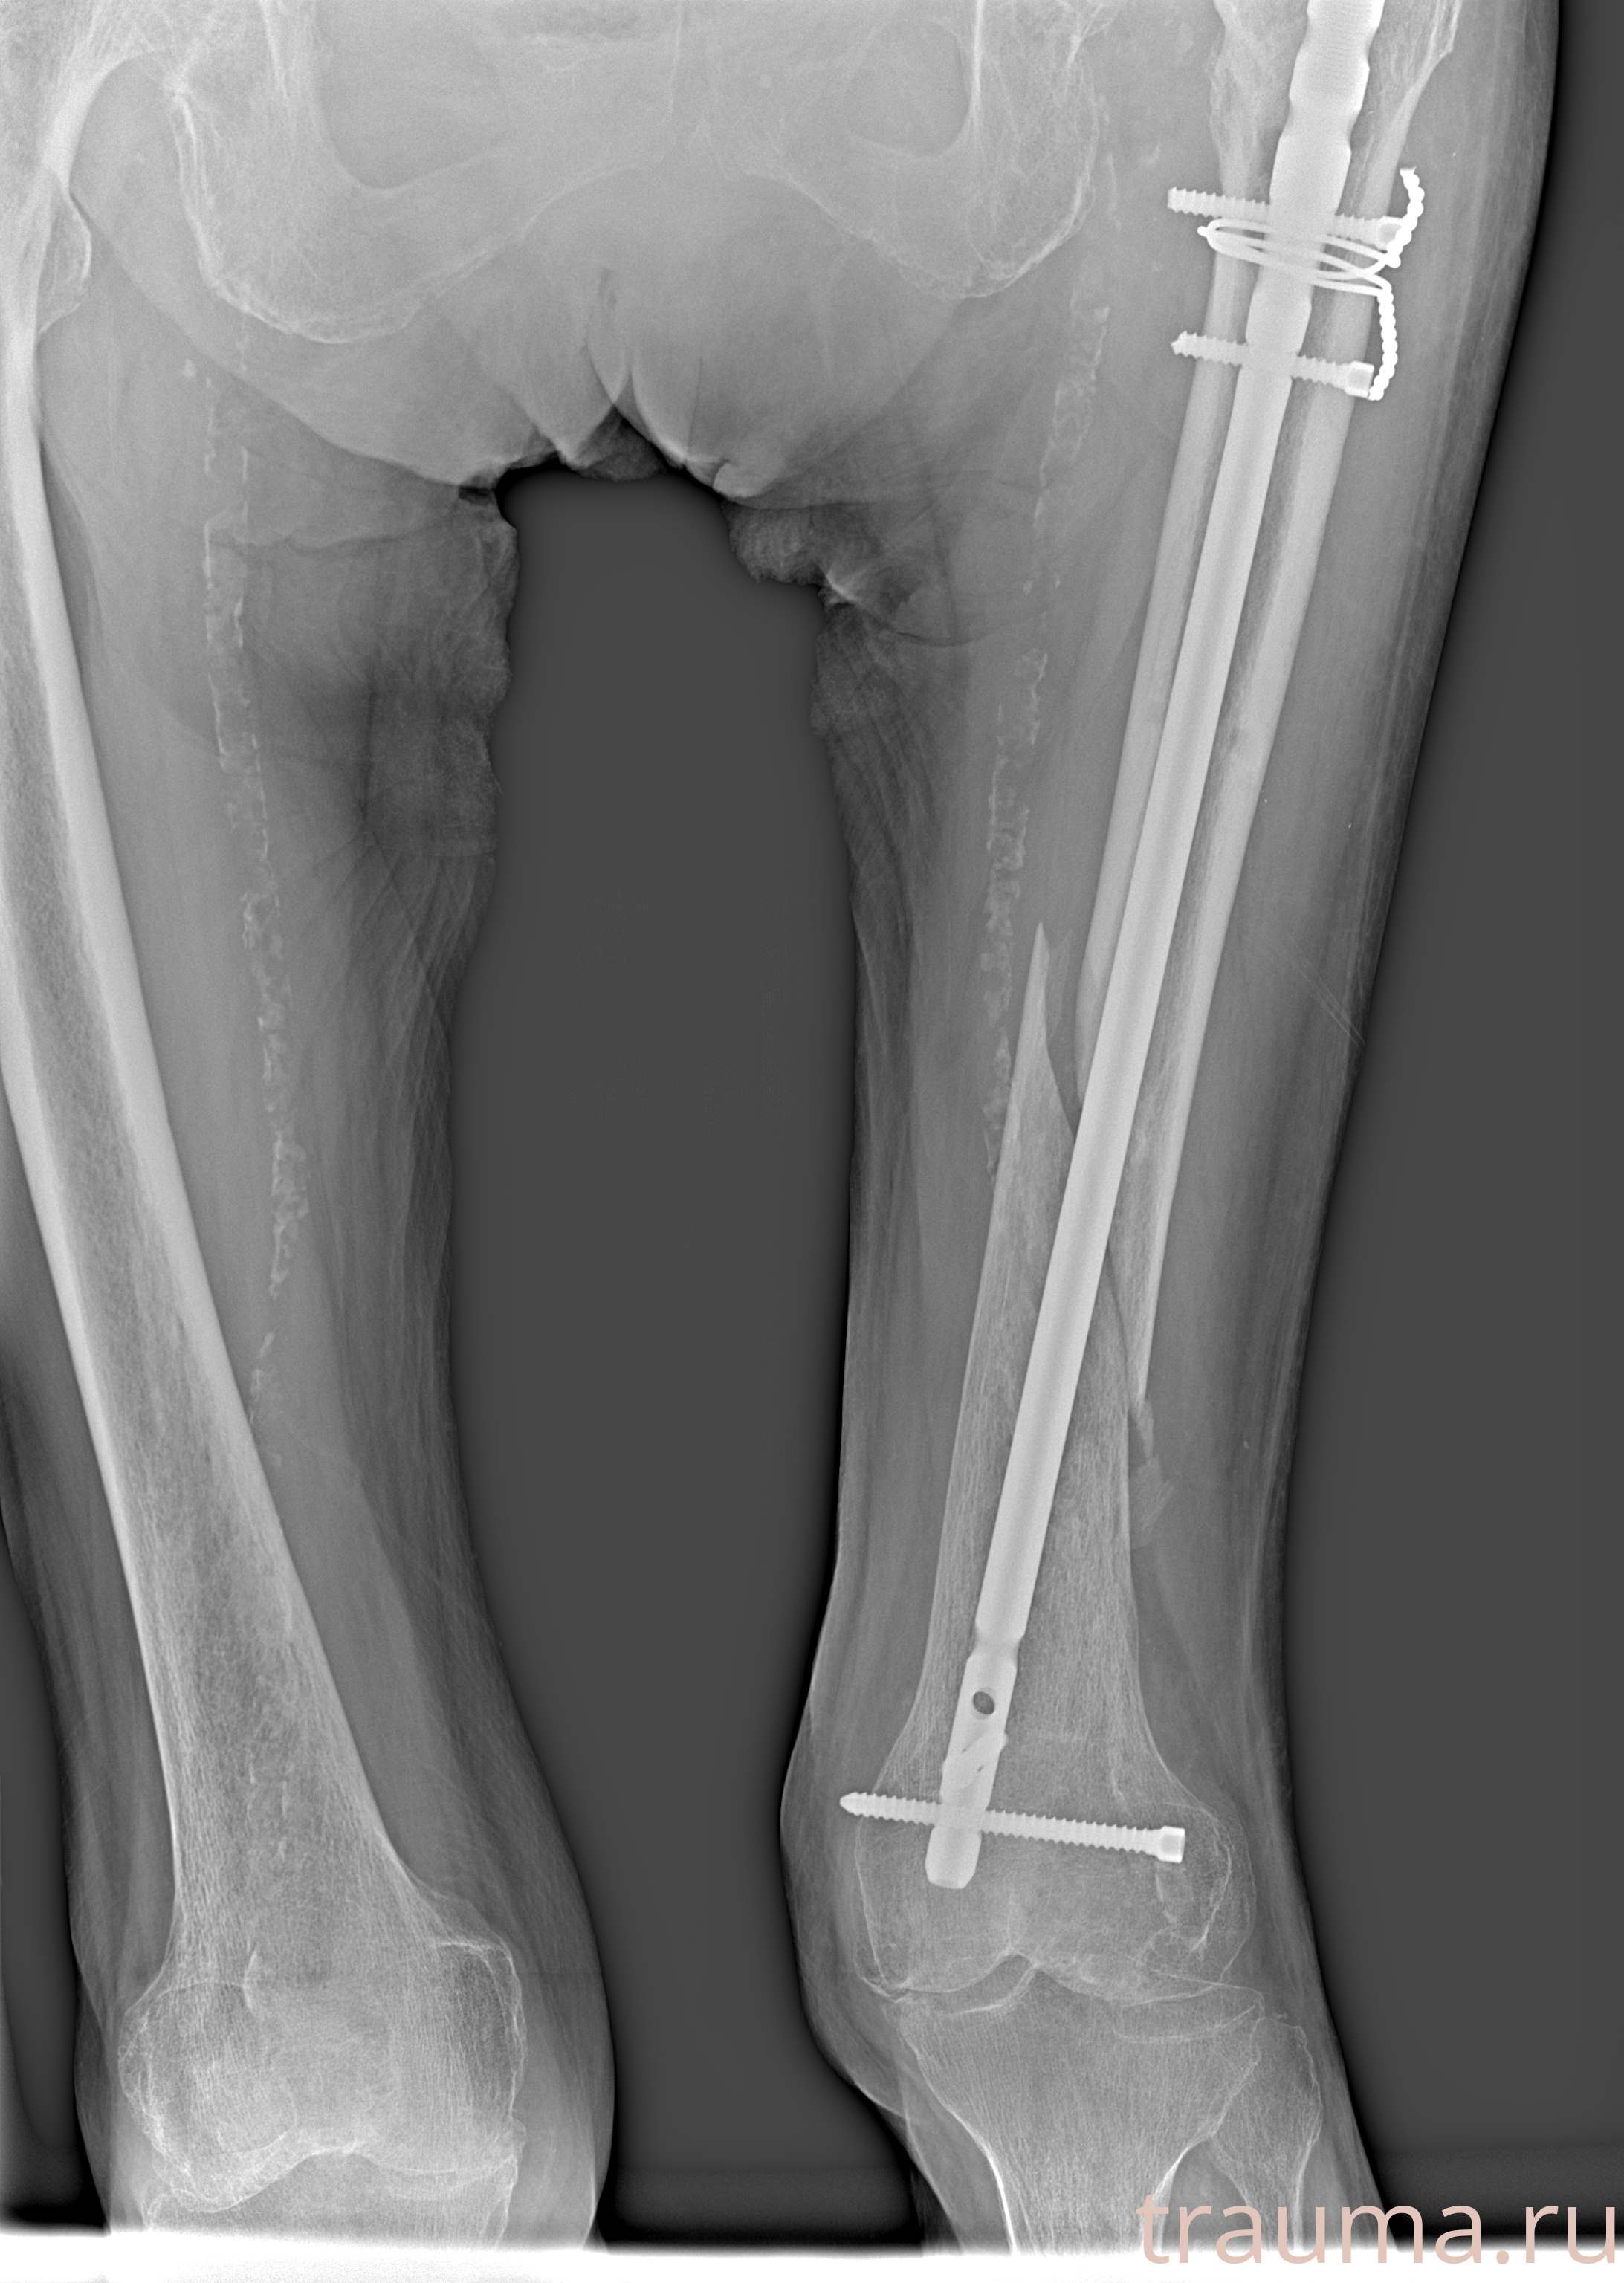

Рентгенограммы

Рентген на дому: по вашему адресу приезжает врач-рентгенолог, травматолог-ортопед с мобильным рентгеновским аппаратом, проводит диагностику травмы или заболевания, делает необходимые рентгенограммы, дает рекомендации по дальнейшему лечению. Получить качественные снимки в домашних условиях возможно благодаря уникальной методике, разработанной МосРентген Центром для института  Склифосовского